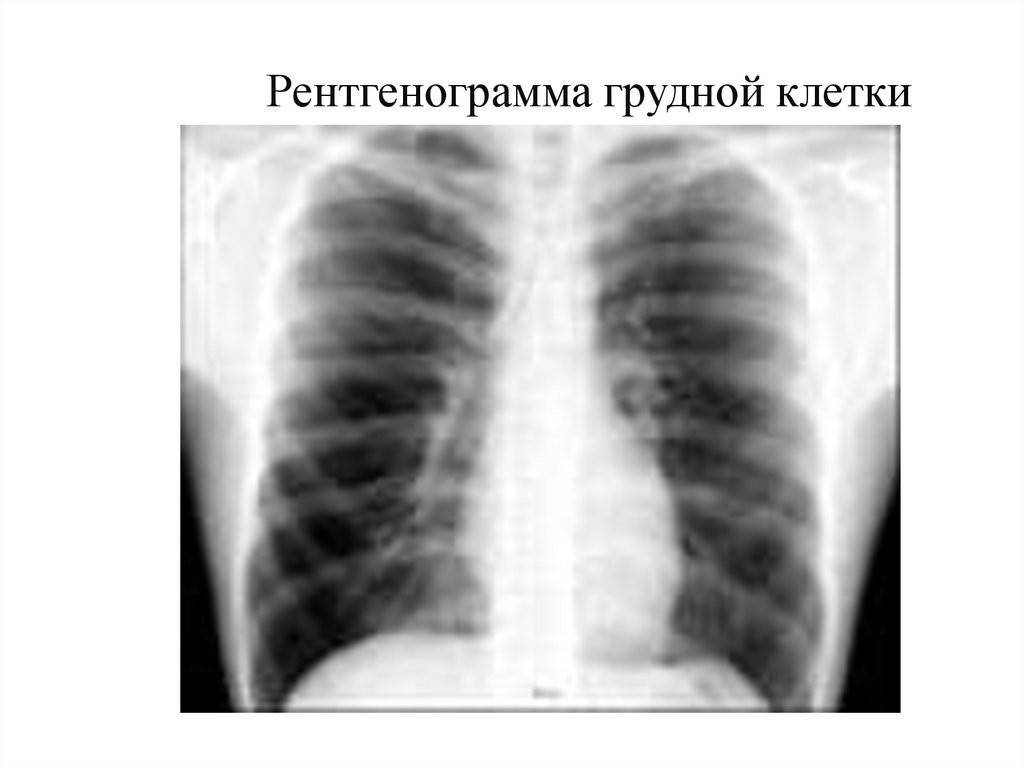

Рентгенограмма грудной клетки

8. Рентгенограмма грудной клетки

9.